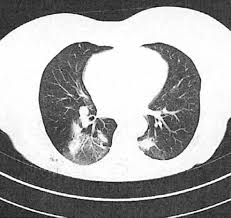

- Рентгенография органов грудной клетки или компьютерная томография (КТ): Визуализация структурных изменений в легких, таких как бронхоэктазы, инфильтраты, кисты.

- Бактериологический посев мокроты: Идентификация патогенных микроорганизмов (например, Pseudomonas aeruginosa, Staphylococcus aureus), колонизирующих дыхательные пути, что важно для выбора антибактериальной терапии.